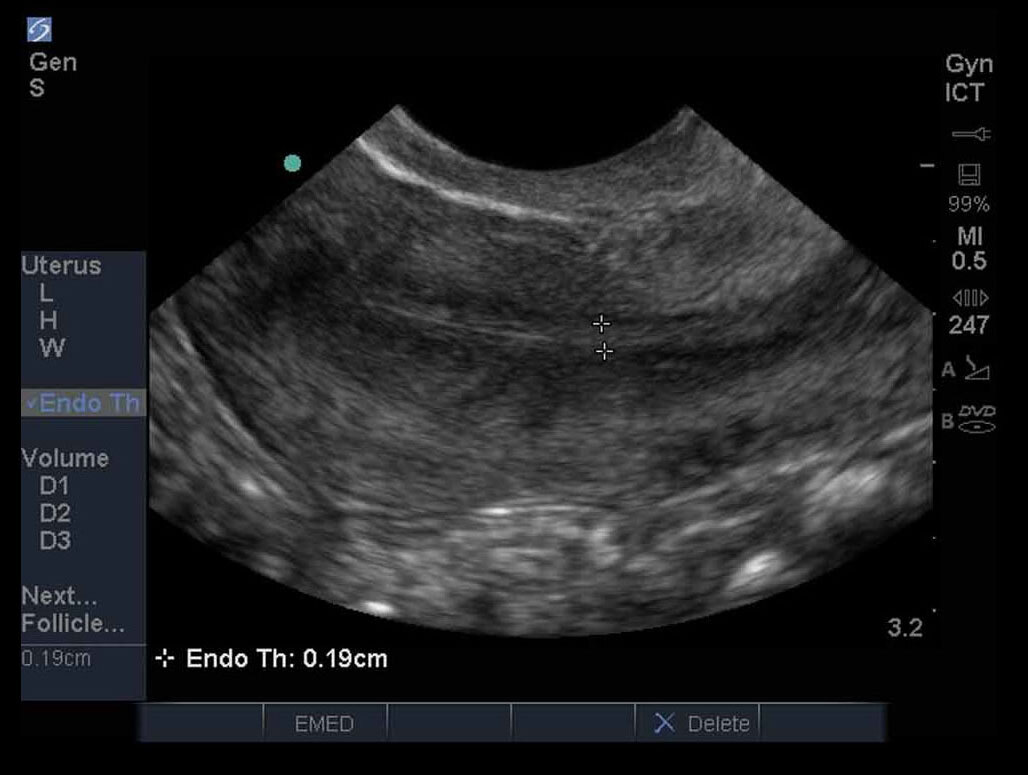

女性の骨盤03画像

M-Turbo:女性ICT 縦断面図1